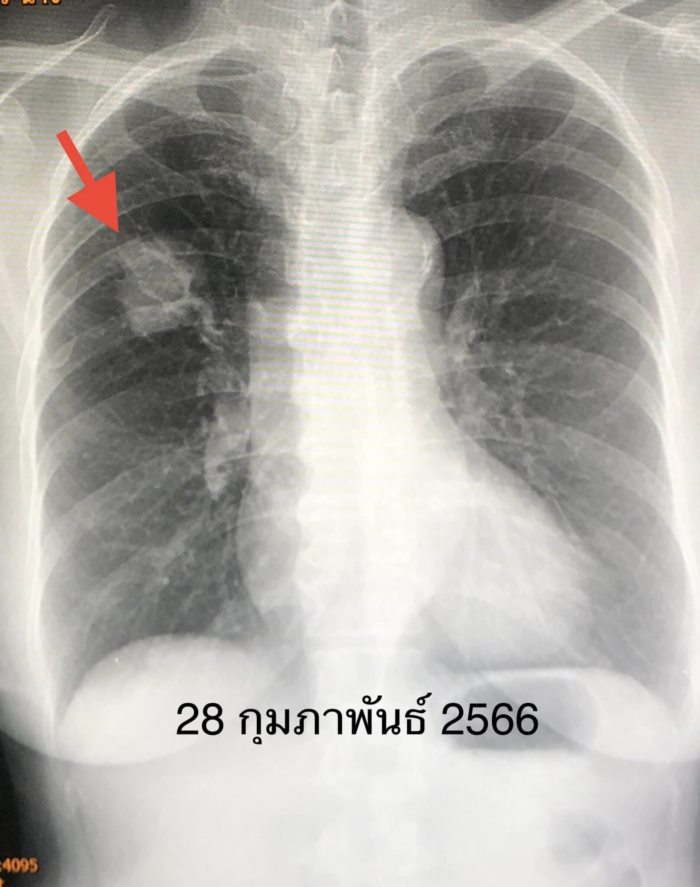

สรุปว่าป่วยเป็นมะเร็งปอดระยะแพร่กระจายแล้ว ผ่าตัดไม่ได้ เนื่องจากเวลานั้นยังไม่มียามุ่งเป้าที่ใช้กับยีนกลายพันธุ์ชนิดนี้ จึงได้เริ่มยาเคมีบำบัดตั้งแต่ต้นเดือนสิงหาคม 2565 โดยให้ยาเคมีบำบัด ALIMTA และ Carboplatin ทั้งหมด 8 ครั้ง ก้อนในปอด เดือนตุลาคม 2565 มีขนาดเล็กลง ต่อมาเดือนมกราคม 2566 ก้อนในปอดกลับโตขึ้นอีก เนื่องจากยาเคมีบำบัดใช้ไม่ได้ผลแล้ว

แพทย์จึงให้คนไข้เข้าโครงการช่วยเหลือให้เข้าถึงยารักษาโรคมะเร็งตัวใหม่ Mobocertinib (Exkivity) ที่โรงพยาบาลรามาธิบดี ให้ขนาด 40 มิลลิกรัม กิน 4 เม็ดวันละครั้งทุกวัน เริ่มเดือนเมษายน 2566 ระยะแรกมีผลข้างเคียงเล็กน้อย มีผื่นและแผลในปาก หลังปรับยาเหลือ 3 เม็ดวันละครั้ง ผลข้างเคียงลดลง เดือน มิถุนายน 2566 หลังกินยา 2 เดือน ผู้ป่วยตอบสนองต่อยาตัวใหม่นี้ดีมาก เอกซเรย์พบก้อนในปอดขนาดเล็กลงมาก ต้องติดตามต่อไปว่า ยาตัวใหม่นี้จะใช้ได้ผลนานแค่ไหน